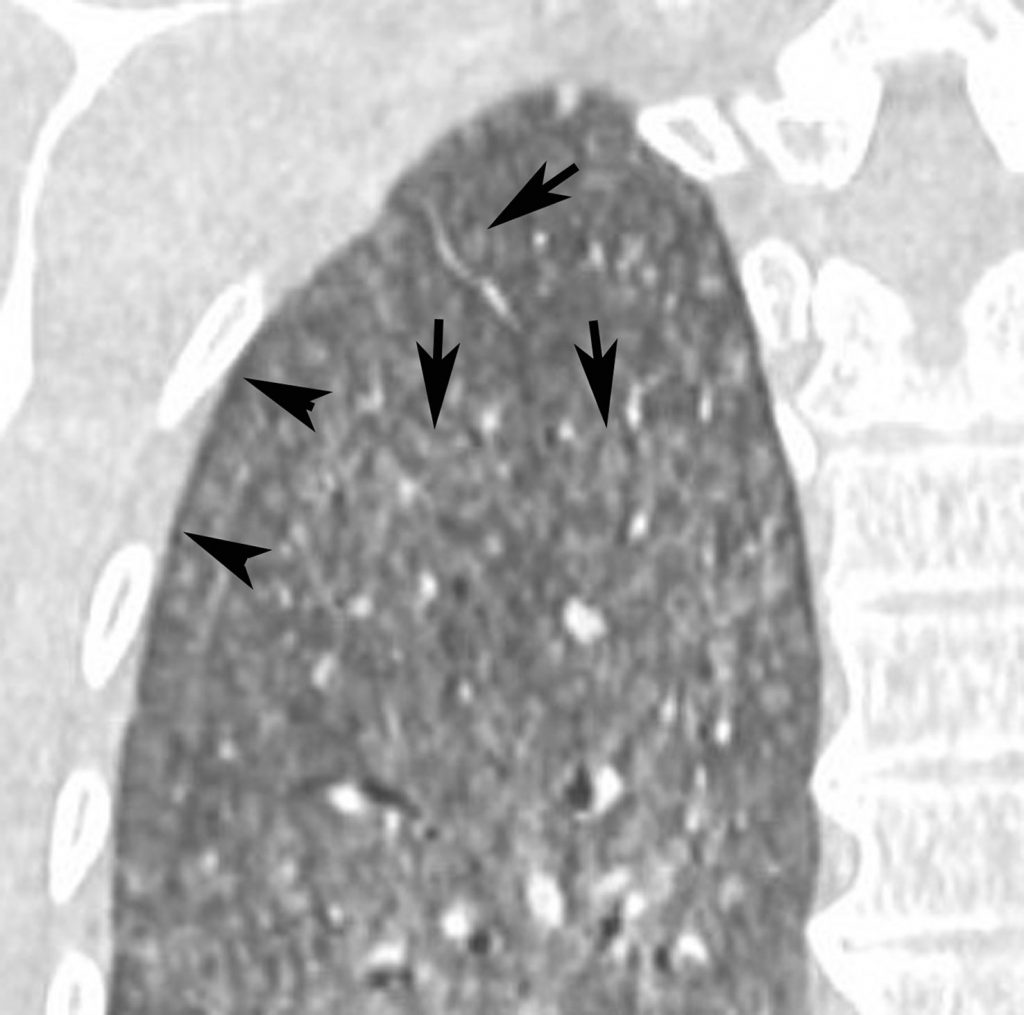

Fig. 97.5. Pneumopathie d’hypersensibilité.

Agrandissement sur le sommet droit d’une coupe frontale. Micronodules à limites floues (flèches) de distribution diffuse dans les deux poumons. Leur topographie centrolobulaire est attestée par l’absence de micronodules sous-pleuraux (têtes de flèches).

Source : CERF, CNEBMN, 2022.